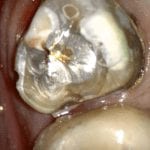

TRY-IN OF EMAX PREMOLAR